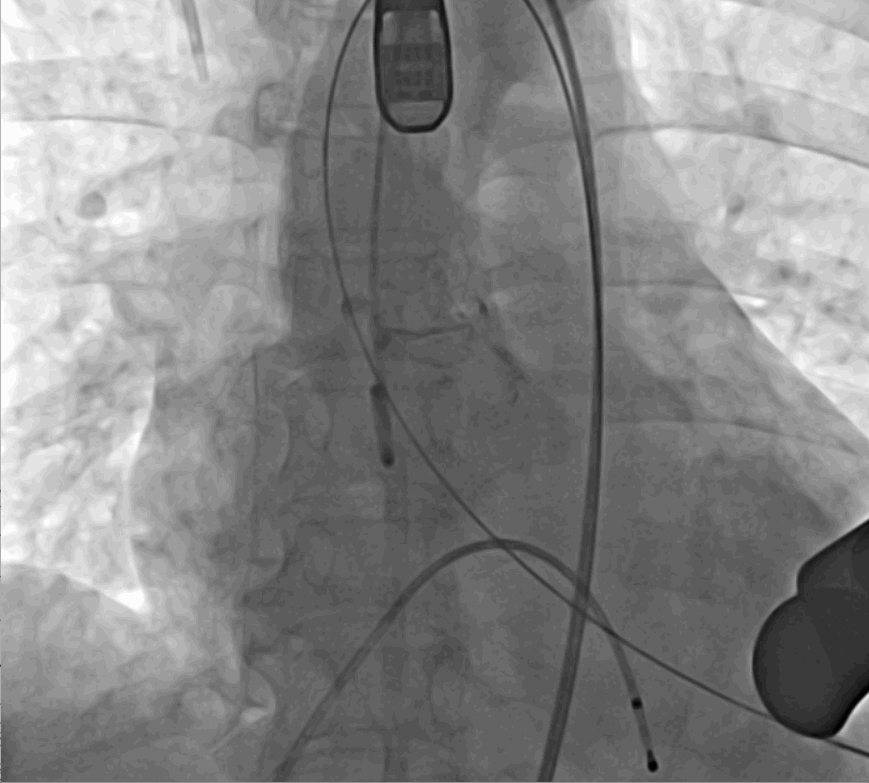

手術(shù)采用經(jīng)心尖入路,對患者進(jìn)行全麻后,在左側(cè)心尖處做3-4cm微創(chuàng)手術(shù)切口,在DSA及超聲引導(dǎo)下手術(shù)順利完成。從導(dǎo)入器械到完成瓣膜置入,僅耗時約10分鐘。術(shù)后即刻主動脈瓣返流程度由術(shù)前大量返流轉(zhuǎn)為消失,患者于導(dǎo)管室拔除氣管插管,次日由ICU轉(zhuǎn)入普通病房。

術(shù)前DSA影像圖